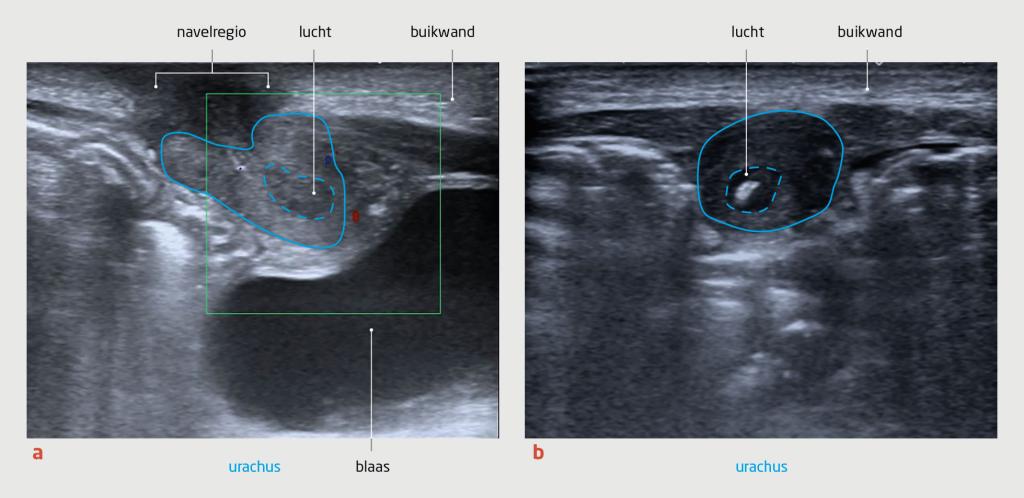

Casus

Wij zagen een zuigeling van 20 dagen met koorts en een rode navel. De werkdiagnose was omfalitis. Na afname van kweken behandelden wij de patiënt met flucloxacilline en gentamicine intraveneus. Vanwege klinische achteruitgang voegden wij ceftazidim toe aan de behandeling en maakten wij een echo van de buik. Hierop zagen wij een restant van de urachus. In de kweek van de naveluitstrijk groeide een Staphylococcus aureus, waarop wij de patiënt verder behandelden met flucloxacilline monotherapie, totdat het infiltraat echografisch was verdwenen.